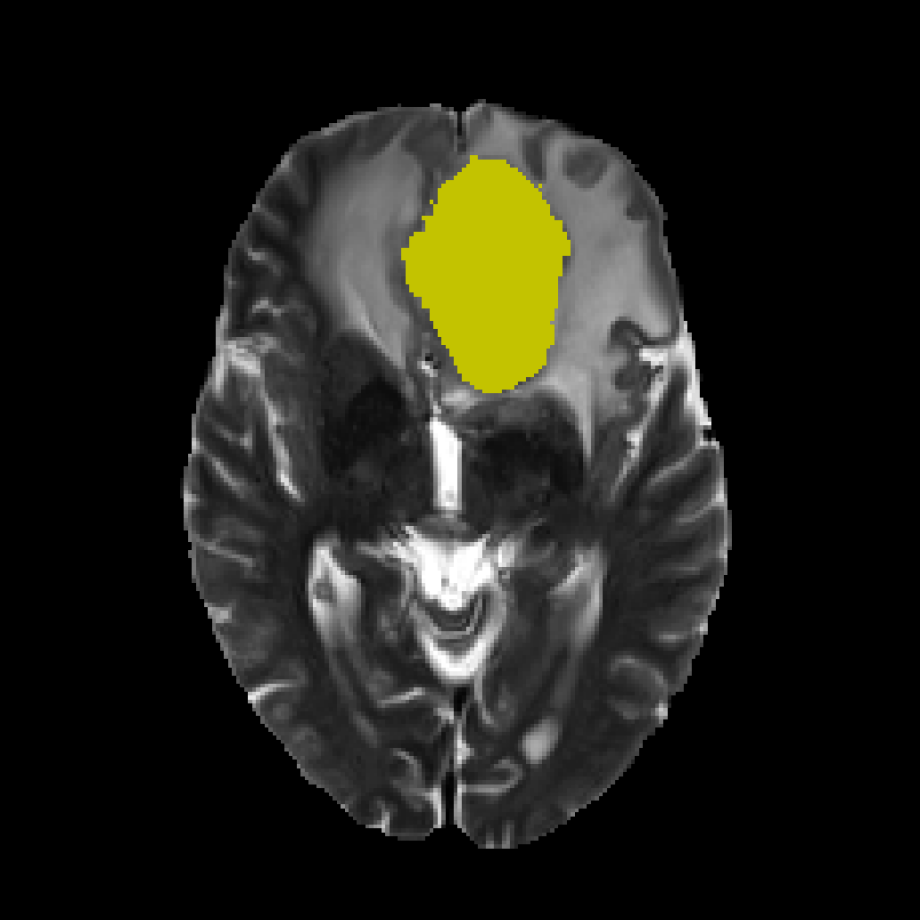

Furthermore, experienced radiologists often analyze multimodal data in clinical practice by designating a primary modality and several auxiliary modalities for pathological diagnosis. This approach is exemplified in the BraTS challenge (Menze et al., 2014) (Figure 2). In this challenge, the segmentation target was the different areas of glioblastoma, which is the most common type of brain malignancy. Glioblastoma is characterized by its resistance to treatment and poor prognosis, making it a critical focus for advancements in medical imaging and treatment strategies(Li et al., 2019). Human annotators primarily employ the T2 modality222T1, T1CE, T2, and FLAIR represent four modalities generated by MRI imaging technology. for segmenting the edema region while using the FLAIR modality to verify the presence of edema and other fluid-filled structures. Subsequently, the tumor core (TC) is identified through the combined use of T1CE and T1 modalities. The expertise of these radiologists suggests that specific mapping relationships exist between modalities and target areas. Certain modalities facilitate the identification of particular area boundaries, while others serve as supplementary aids. Gleaning insights from this expert knowledge and incorporating it as an inductive bias can potentially reduce the complexity of learning relationships between modalities and corresponding regions. A similar example of adding priors to reduce learning difficulty is DetexNet (Liu et al., 2020), which simplifies low-level representation patterns by embedding expert knowledge.

To describe task decomposition more clearly, we take BraTS2020 as an example. As illustrated in Fig.3, the original multi-target task is divided into four distinct sub-tasks. The sub-tasks involve utilizing FLAIR as the primary modality for segmenting the whole tumor (WT) region, employing T1 as the primary modality for segmenting both the tumor core (TC) and the enhanced tumor (ET), leveraging T2 as the primary modality for segmenting the WT and TC regions and adopting T1CE as the primary modality for segmenting the TC and ET regions. This task decomposition is based on expert prior knowledge, which suggests that the selected primary modalities contain the most informative features for accurately segmenting their respective target regions. In addition, to test the performance of different decompositions, we designed ablation experiments to compare several different decomposition methods, as detailed in Section 4.